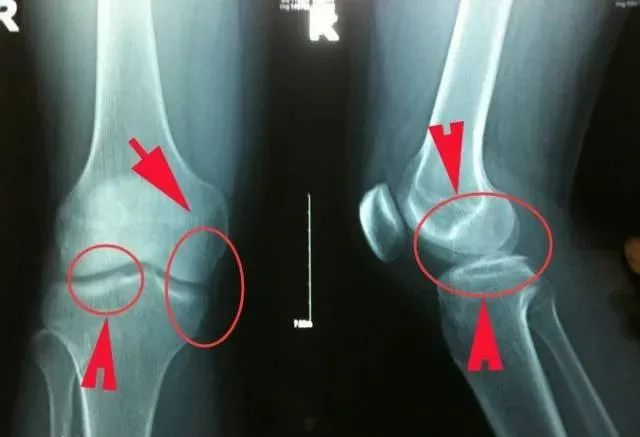

3、骨骺板(生长板)

骨骼板处于骨骼连接处的两端,随着年龄的增长,它们会不断硬化

适当的健身运动,可以促进骨骺的增生